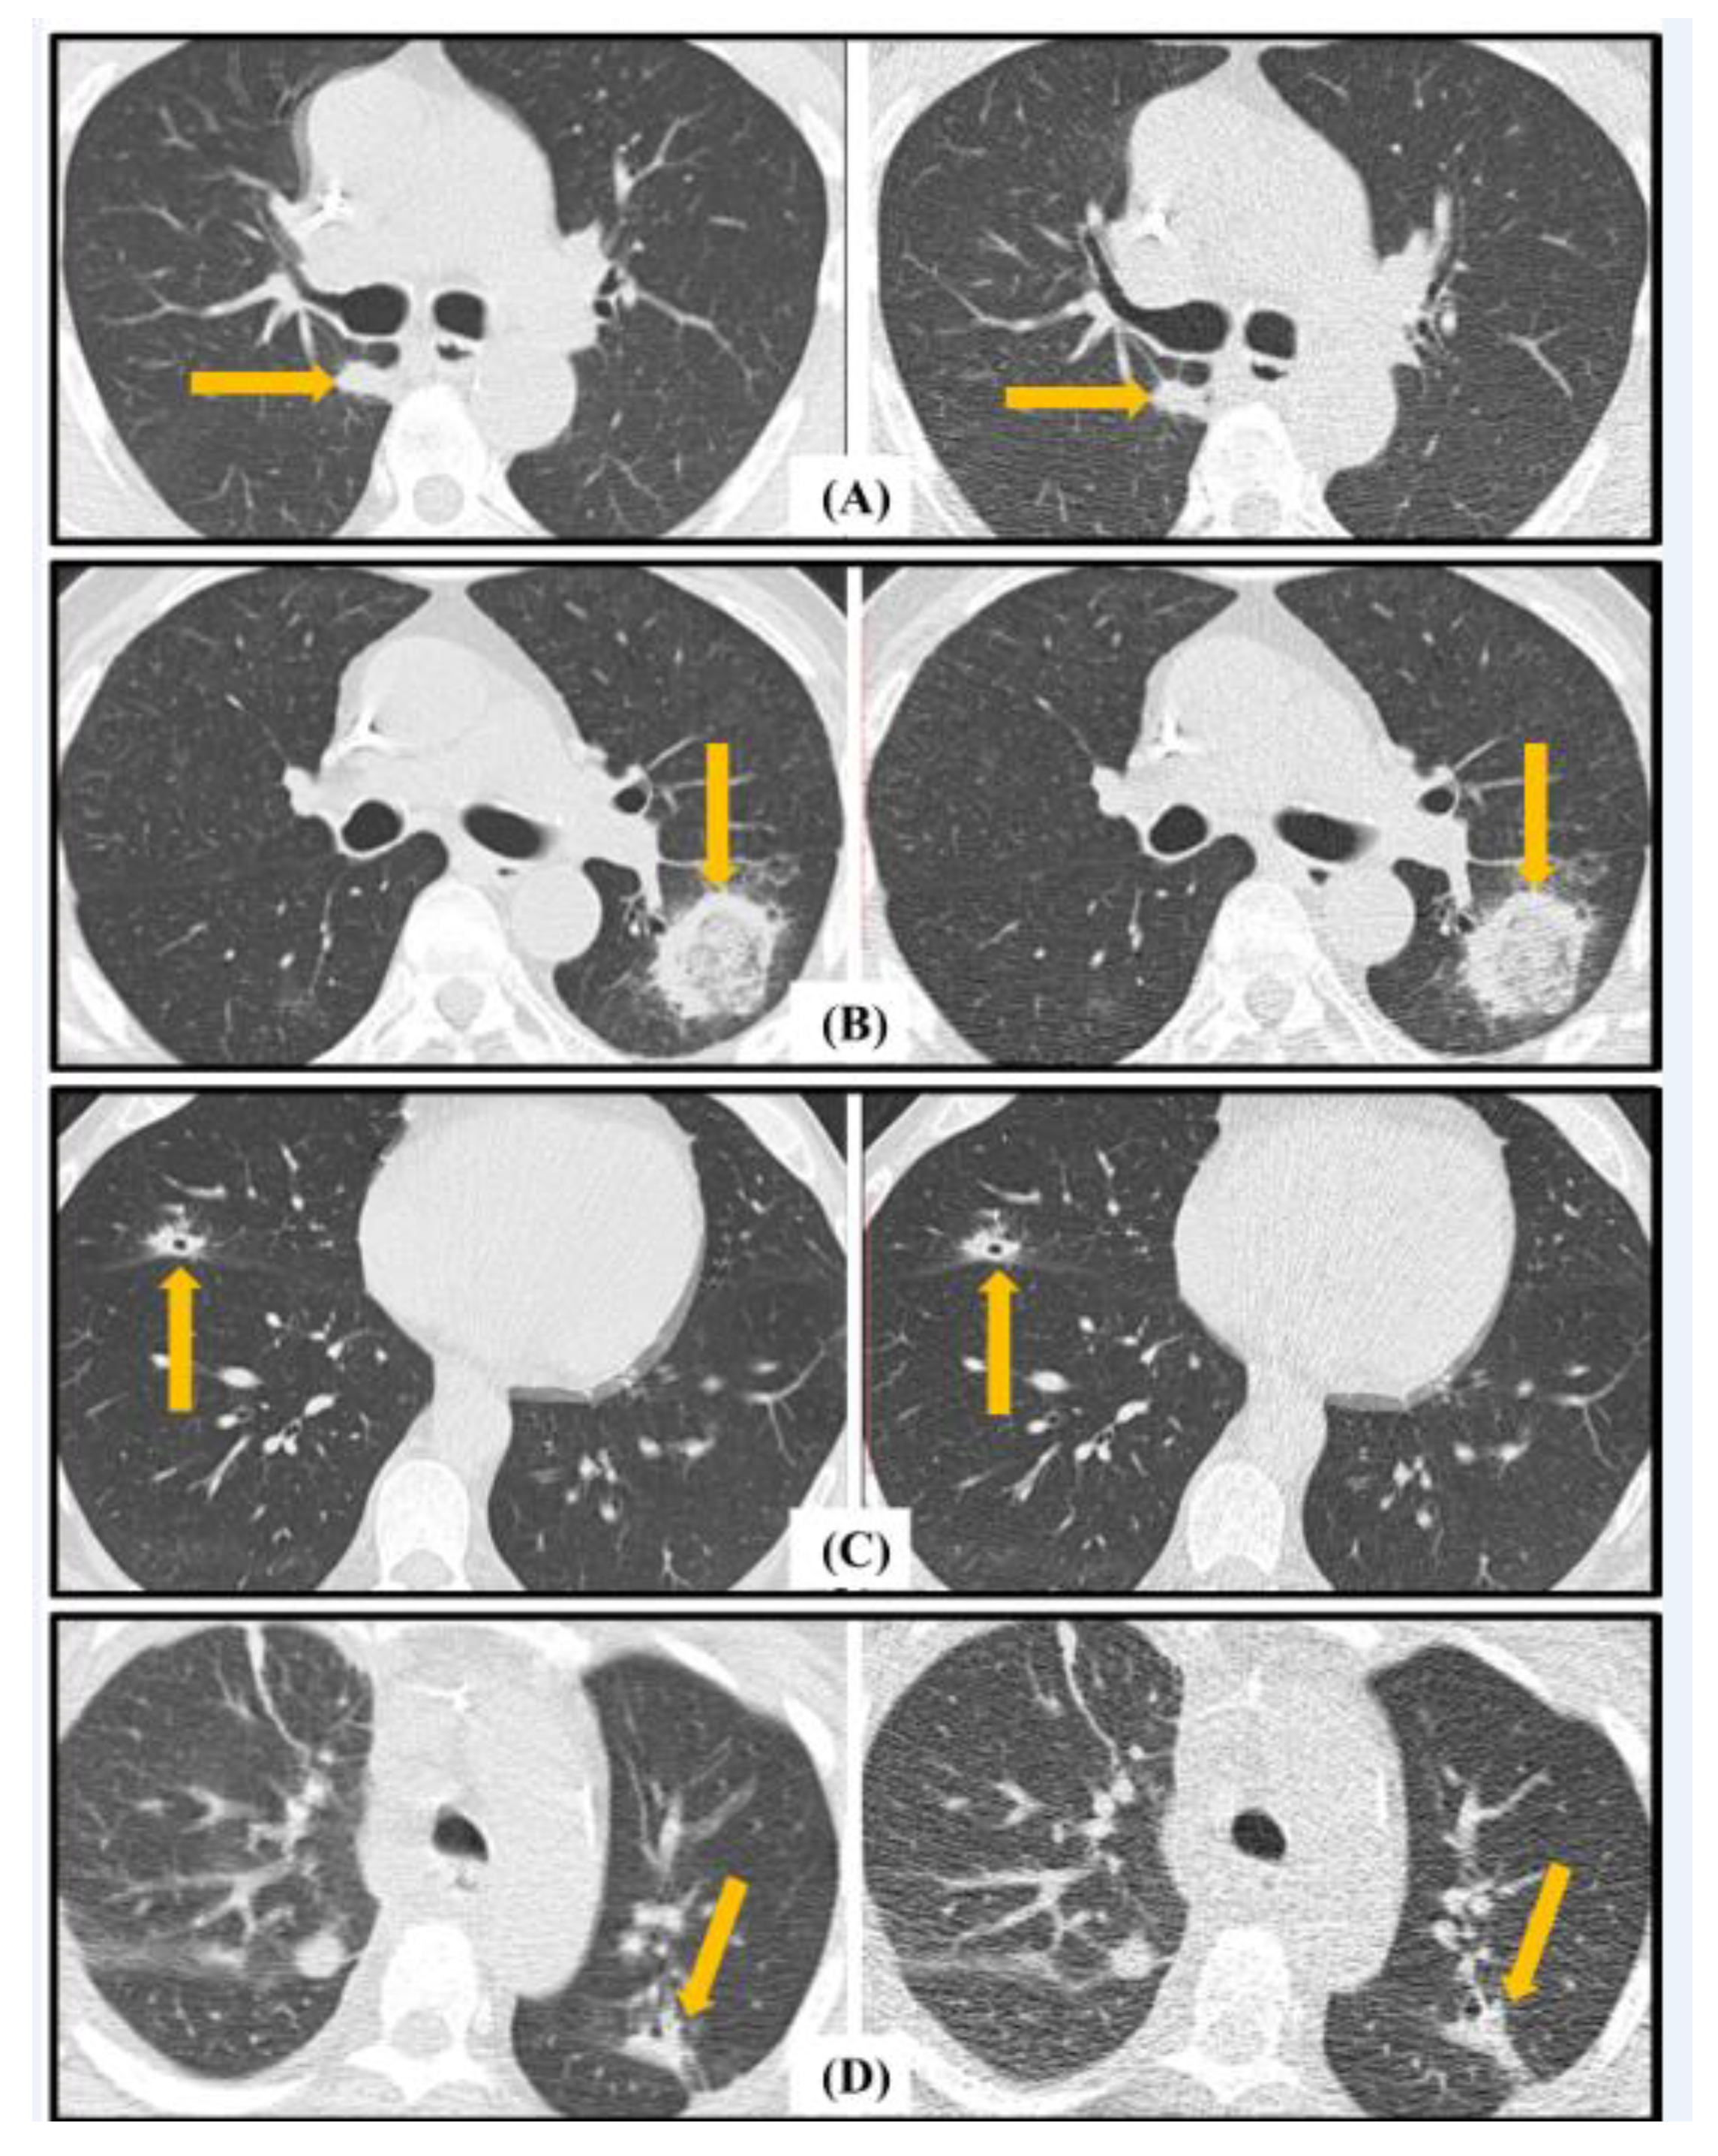

4.3. EORTC Radiological Findings Assessment

| Any Major Radiological Sign * | 24 | 2 | 2 | 72 | 92.3% | 97.3% | 96.0% |

| Macro Nodule | 4 | 0 | 0 | 96 | 100% | 100% | 100% |

| Halo Sign | 2 | 1 | 0 | 97 | 66.7 | 100.0 | 99.0 |

| Cavitation | 2 | 0 | 0 | 98 | 100.0 | 100.0 | 100.0 |

| Consolidation | 22 | 2 | 3 | 73 | 91.7 | 96.1 | 95.0 |

| Any Minor Radiological Sign * | 71 | 13 | 3 | 13 | 84.5% | 81.3% | 84.0% |

| Nodules (4–10 mm) | 49 | 13 | 8 | 30 | 79.0 | 78.9 | 79.0 |

| GGO | 56 | 16 | 3 | 25 | 77.8 | 89.3 | 81.0 |